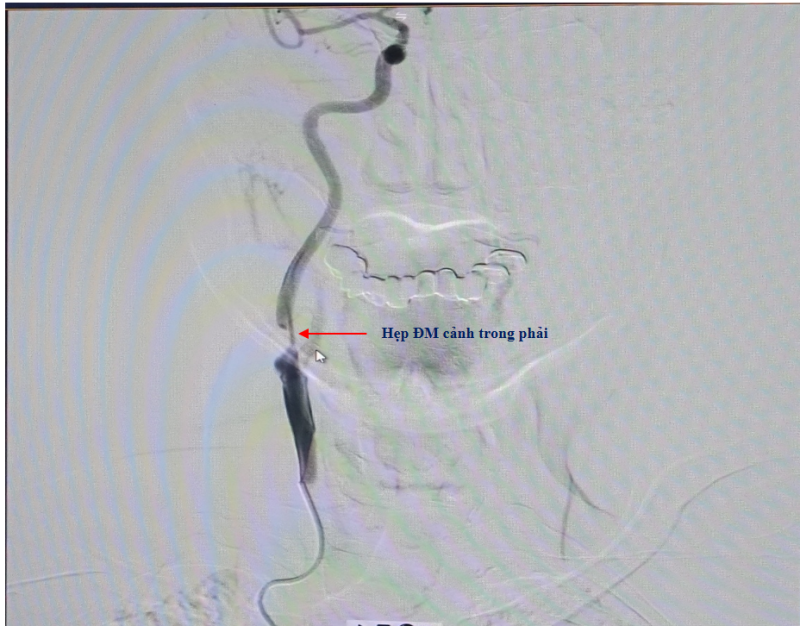

Để đánh giá chính xác tổn thương, bệnh nhân được chỉ định chụp mạch máu não bằng phương pháp chụp mạch số hóa xóa nền (DSA). Kết quả cho thấy gốc động mạch cảnh trong bên phải bị hẹp rất nặng, khoảng 90%. Đây là một trong số nguyên nhân chính gây giảm tưới máu bán cầu não phải, dẫn đến tình trạng yếu liệt nửa người trái của bệnh nhân.

Hình ảnh: Trước can thiệp